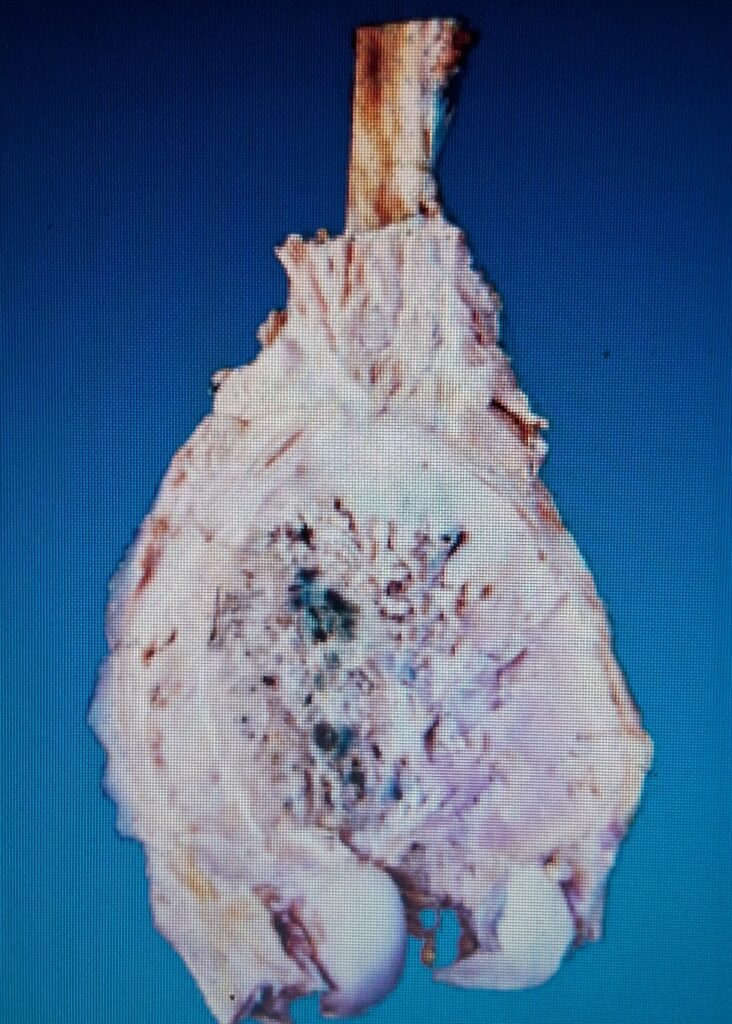

Osteosarcoma or osteogenic sarcoma is most common primary malignant tumour of bone. The tumour is characterised by formation of osteoid or bone, or both, directly by sarcoma cells

The tumour is thought to arise from the primitive osteoblast-forming mesenchyme. Depending upon their locations within the bone, osteosarcomas are classified into 2 main categories: central (medullary) and surface ( parosteal and perosteal)

This is the more common and classic type and is generally referred to as β€˜osteosarcoma’ if not specified. The tumour occurs in young patients between the age of 10 and 20 years. Males are affected more frequently than females.